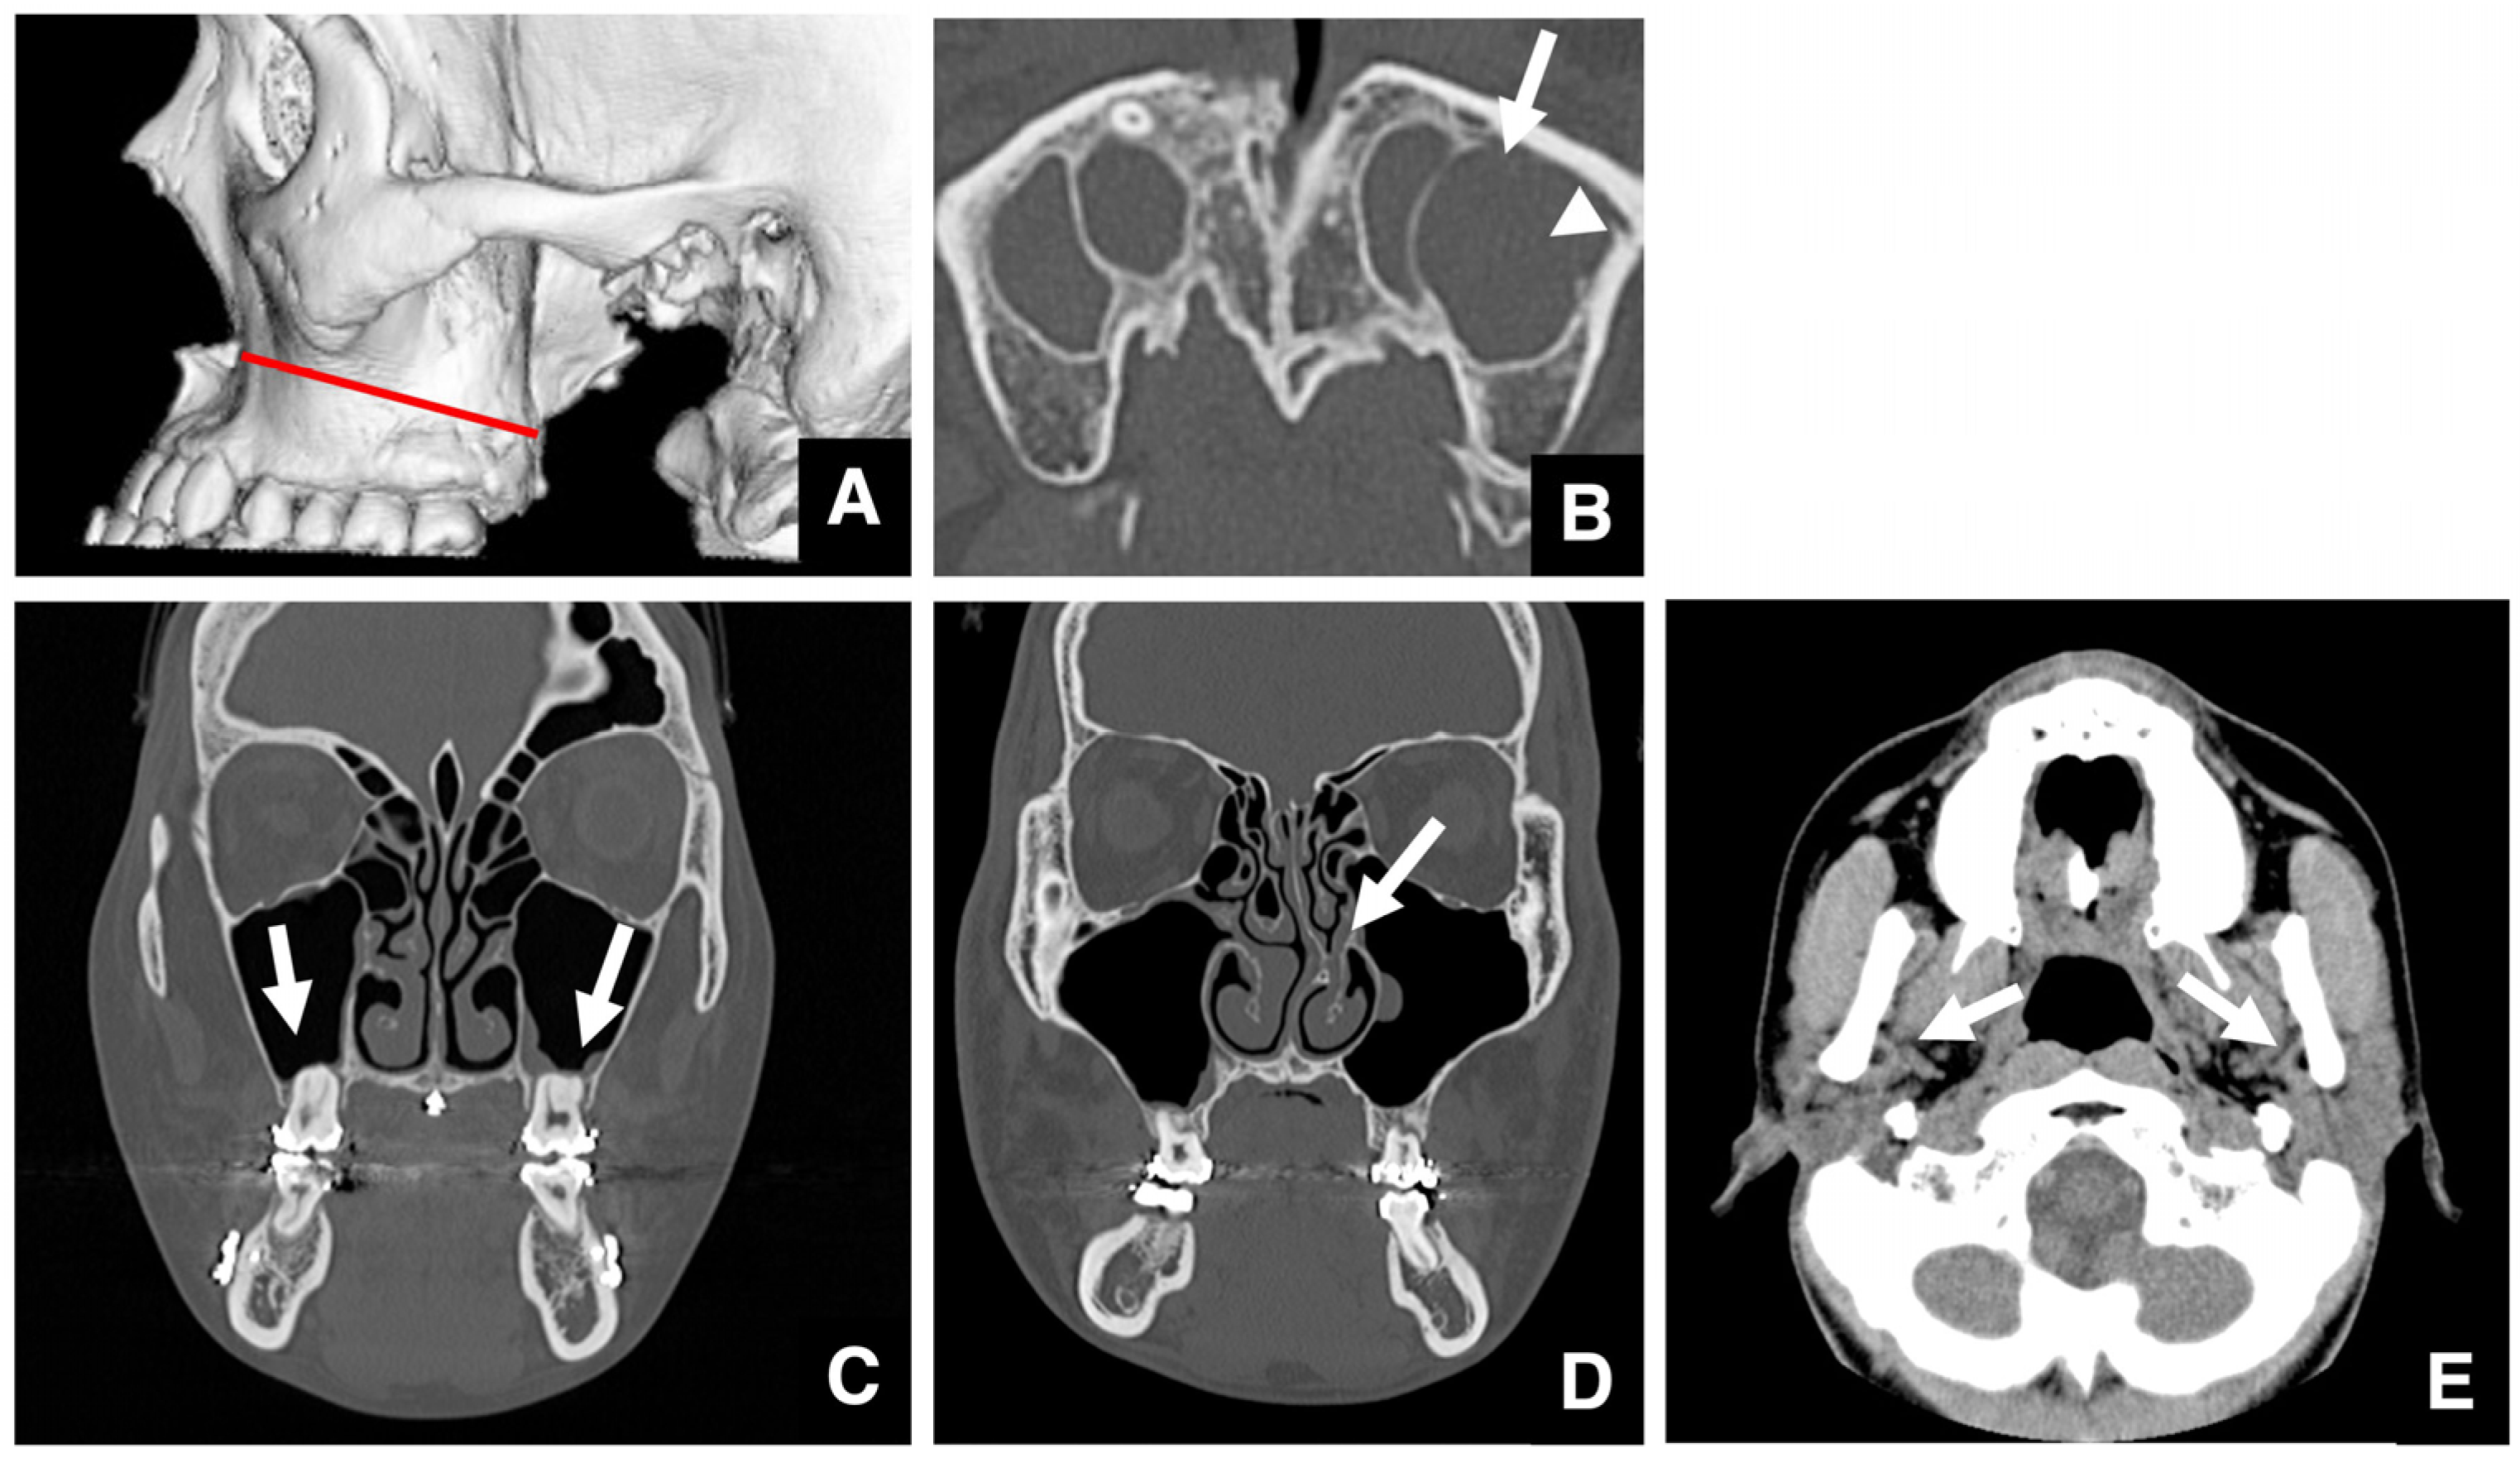

| Improving safety through prediction of surgical difficulty and complication 1. Circumstance of pterygoid venous plexus Carefully observe the fat tissue surrounding the medial and lateral pterygoid muscles to assess the development of the internal vascular structures (using CT and MR to evaluate the size of the fat tissue) 2. Fusion status of the maxillary tuberosity and pterygomaxillary suture When the fusion is narrow and the degree of calcification (CT number) is low or when the fusion is wide and high 3. Course of the descending palatine artery and thickness of surrounding bone When the palatal canal wall is thick, the probability of damage during transection is low. When it is thin, the possibility of damage cannot be ruled out. Setting the osteotomy line 1. Distance from the piriform rim to the greater palatine canal Long, short, cortical bone thickness, presence or absence of bone irregularities 2. Evaluation of the size, morphology, and internal features (mucosa, septa, etc.) of the maxillary sinus Size, shape, presence or absence of septa, presence or absence of masses, presence or absence of mucosal thickening 3. Relationship between the floor of the maxillary sinus and the apices of the molars Describe the maxillary sinus floor and the apex of each molar tooth 4. Presence of nasal septal deviation, size of the nasal passages, and thickness of the lateral nasal wall bone Presence or absence of nasal septal deviation, Size of the nasal passage, Thickness of the cortical bone of the lateral wall 5. Course of the mandibular artery The course from the pterygoid cleft to the pterygopalatine fossa in the posterior maxilla |

- Eshghpour, M.; Mianbandi, V.; Samieirad, S. Intra- and postoperative complications of Le Fort I maxillary osteotomy. J. Craniofac. Surg. 2018, 29, e797–e803. [Google Scholar] [CrossRef]

- Niazi, M.H.; El-Ghanem, M.; Al-Mufti, F.; Wajswol, E.; Dodson, V.; Abdulrazzaq, A.; Sami, T.; Nuoman, R.; Aziz, S.; Gandhi, C.D. Endovascular management of epistaxis secondary to dissecting pseudoaneurysm of the descending palatine artery following orthognathic surgery. J. Vasc. Interv. Neurol. 2018, 10, 41–46. [Google Scholar] [PubMed]

- Ulker, O.; Demirbas, A.E.; Kutuk, N.; Kilic, E.; Alkan, A. Vascular complications in Le Fort I osteotomy: Incidence, reasons, and management of the intraoperative hemorrhage. J. Craniofac. Surg. 2021, 32, 325–328. [Google Scholar] [CrossRef] [PubMed]

- Yun, Y.; Kurasawa, S.; Morita, M.; Kawachi, R.; Murata, H.; Sawada, S.; Kojima, Y.; Yagi, M.; Asako, M.; Iwai, H. Postoperative hemorrhage after Le Fort I osteotomy hemostasis with angiographic embolization: Report of two cases. J. Surg. Case Rep. 2023, 12, rjad663. [Google Scholar] [CrossRef] [PubMed]

- Pereira-Filho, V.A.; Gabrielli, M.F.; Gabrielli, M.A.; Pinto, F.A.; Rodrigues-Junior, A.L.; Klüppel, L.E.; Passeri, L.A. Incidence of maxillary sinusitis following Le Fort I osteotomy: Clinical, radiographic, and endoscopic study. J. Oral Maxillofac. Surg. 2011, 69, 346–351. [Google Scholar] [CrossRef]